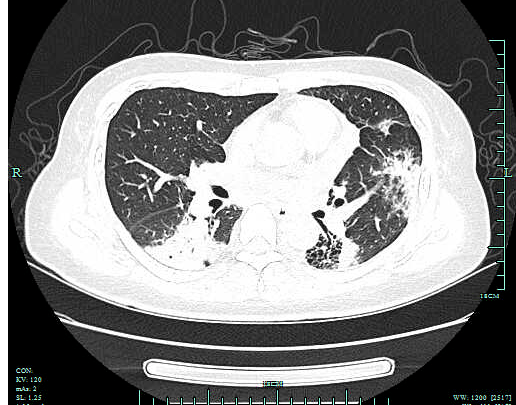

李琴(化名) , 女 , 47岁 , 因间断发热10天 , 胸闷、气喘加重1天收 住我院呼吸重症监护室 。 入院肺部CT提示两肺上叶、下叶背段多发感染 , 左肺下叶少许间质纤维化伴间质性炎症 , 两侧胸腔积液 。 入院予以无创辅助通气(高流量氧支持) ,积极抗感染、补液、纠正内环境等对症支持治疗 , 效果欠佳 , 在院期间完善痰、尿、便检验及院外肺泡灌洗液NGS , 均未寻找到可靠病原学依据来指导临床 。鉴于患者病情危重 , 治疗效果不理想 , 感染病因难以明确 , 预后较差 , 经 家属同意 , 医师在床旁行“超声定位引导下右肺穿刺活检术” , 后期 随访病理诊断:机化性肺炎 。 后经系统治疗患者临床症状改善 , 好转出院 。